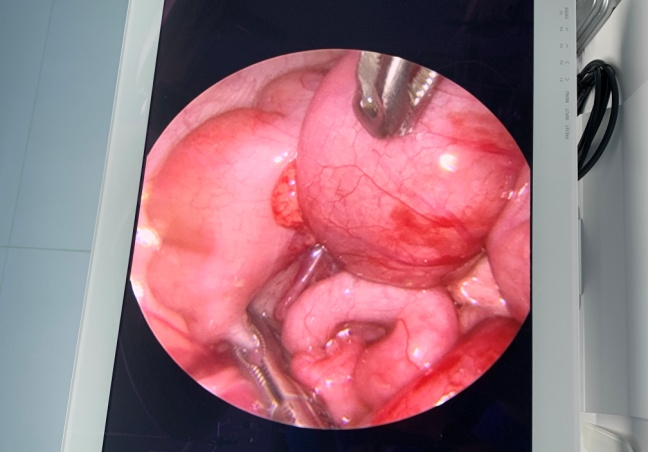

近日,我院为一名仅7月龄的患儿成功完成了九江市首例腹腔镜下肠套叠复位术。

8 月 20 日 21 时许,这名 7 月龄患儿因阵发性剧烈腹痛、哭闹不安,同时伴血便 12 小时被我院八里湖院区儿外科收治,考虑急性肠套叠。科主任郭秋鹏立刻赶到医院为患儿进行查体,鉴于孩子年龄小,与家属详细沟通后,商议拟定在腹腔镜下行肠套叠复位术。迅速做好相关术前准备后,手术过程非常顺利,整个接诊到术后,团队衔接默契,以最快时速为患儿解除了病痛。目前患儿恢复状况良好,患儿家属对我院儿外科医护团队的精湛医术和精心护理深表认可。

腹腔镜手术:近年来逐渐成熟,术后恢复快,疤痕小,疼痛轻,但中转手术比例也较高,对医生要求极高。